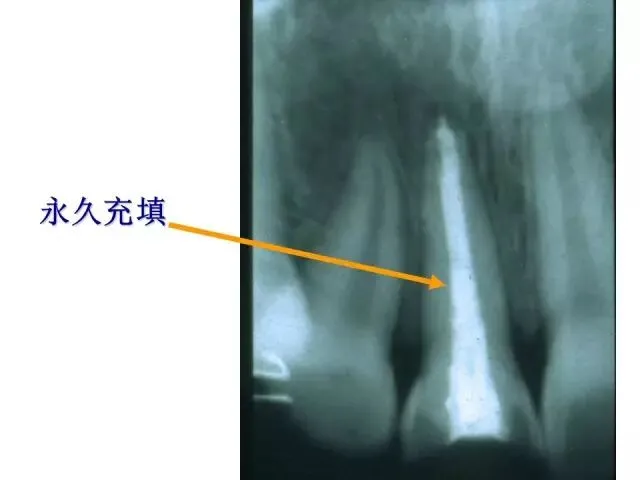

>PPT典藏 | 根尖诱导成型术

PPT典藏 | 根尖诱导成型术